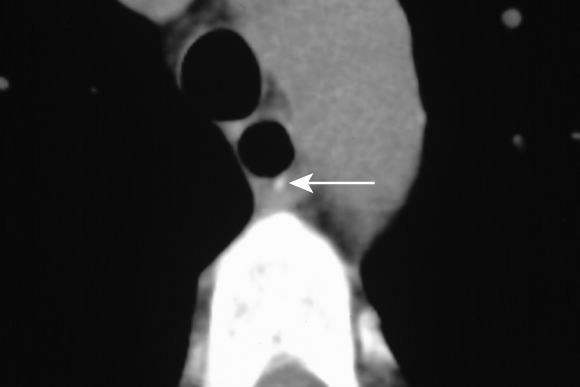

The patient was admitted and managed with nil by mouth, intravenous fluids, triple intravenous antibiotic therapy (ampicillin 1 g four times a day, gentamicin 5 mg/kg daily [with subsequent doses titrated according to drug level], metronidazole 500 mg twice a day), intravenous omeprazole 40 mg three times a day, and frequent observation. Her fever resolved within 24 hours, but her C-reactive protein level rose to 18.2 mg/L (reference range, 0–8.0 mg/L). A second CT scan, with water-soluble contrast, showed intramural contrast with no extravasation, consistent with a partial perforation of the oesophagus (Box 1). Gastroscopy revealed a 10 cm longitudinal mucosal/submucosal tear in the left posterolateral wall of the oesophagus 3 cm above the gastro-oesophageal junction (Box 2A), and a small sliding hiatus hernia. The rest of the oesophagus, stomach and duodenum were normal.